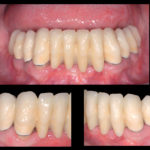

Gestione dinamica e analisi estetica dei trattamenti di denti vitali nel settore anteriore: anestesia...

Afronte del continuo sviluppo di nuovi sistemi adesivi, nonché di nuovi materiali compositi e ceramici in odontoiatria, la gamma di indicazioni cliniche per tutti...